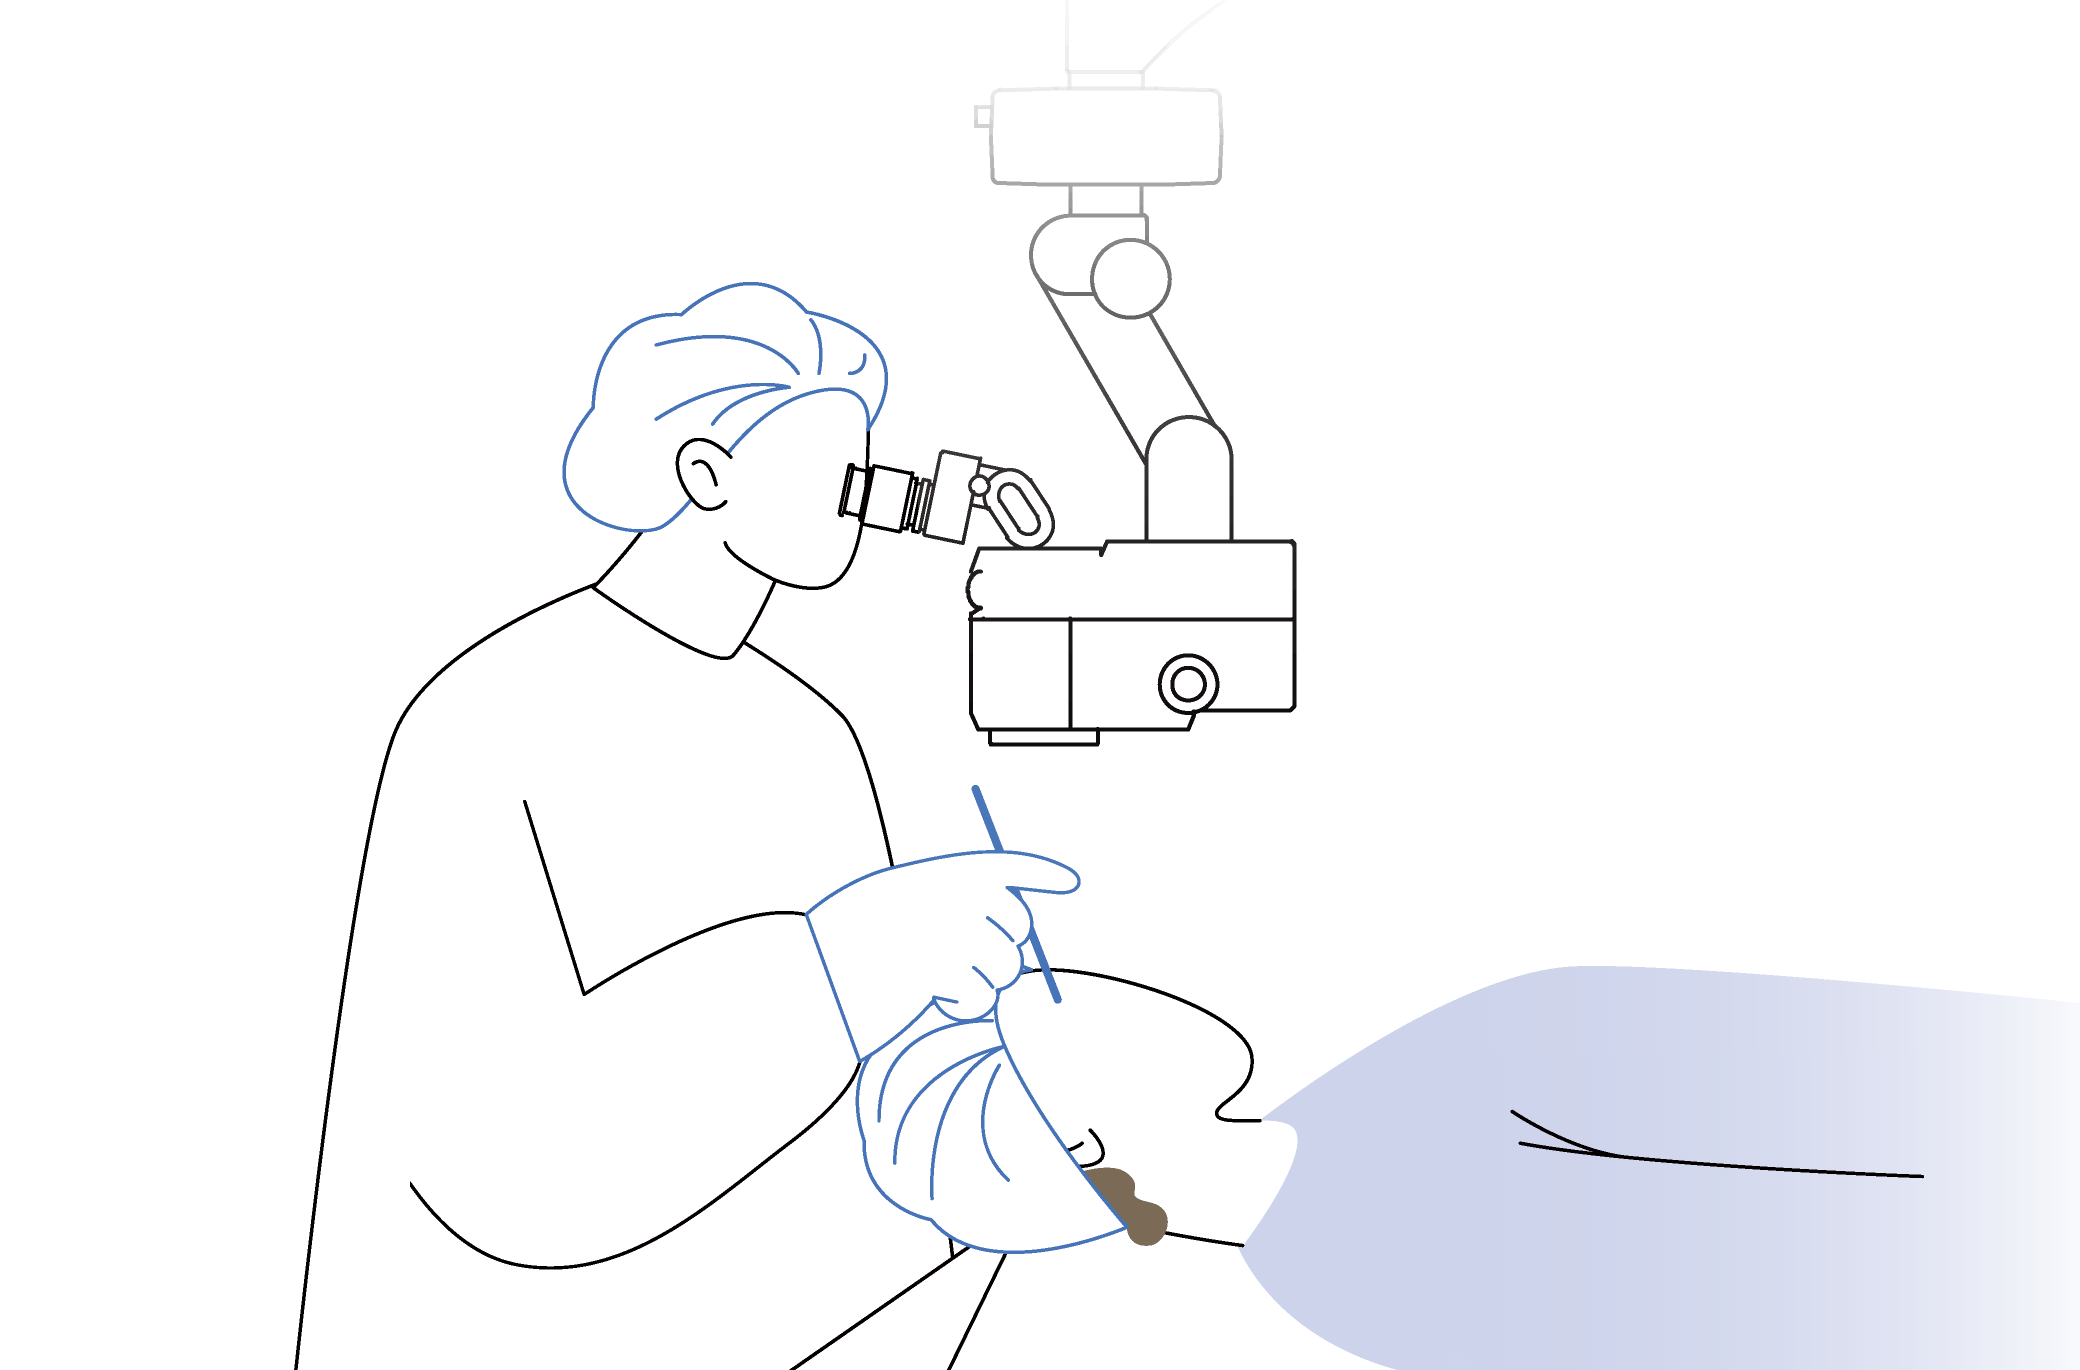

Operating Microscopes

OM-19

Supports a wide range of surgeries, from cataract surgery to retinal vitrectomy.

Independent light sources provide a wide range of illumination.

Flexible customization with a rich variety of options.